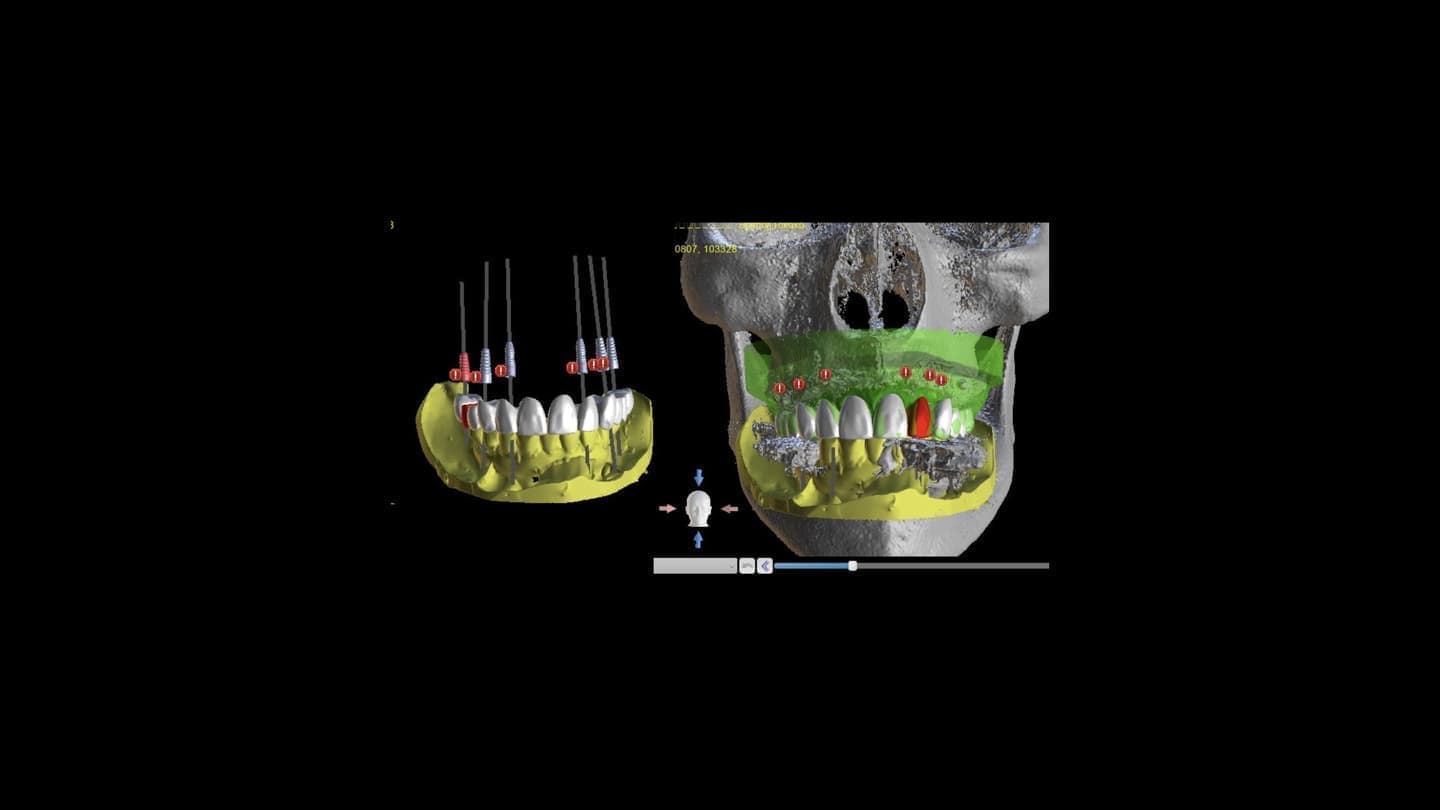

CT診断、CAD/CAMを活用した最先端の治療を行います

インプラント治療は失ってしまった歯の替わりに、 生体親和性が極めて高い純チタンで出来たインプラント(人工歯根)を歯肉内部にある顎の骨に埋め込み、その上に人工の歯を取り付け、噛み合わせを回復する治療法です。

CT設備完備

二次元のレントゲン(歯科医院にある通常のレントゲン)では見えなかったこと、分からなかったことが、歯科用CTなら正確な診査と診断ができ、安全性と治療のクオリティーを高めることが可能となります。

インプラント手術においてCT撮影は必須です。CT撮影を行うか否かも医院を選ぶうえでの判断材料にしていただければと思います。

ンピューター診断

手術時の「人為的なミス」を最小限に抑えることができる安全なインプラント治療を望まれる方。ぜひ、コンピューターインプラントを実施している医院での受診を強くお勧めします。

科手術

術前の診断を手術に生かします。

シュミレーションした場所に確実にインプラントを設置していきます。